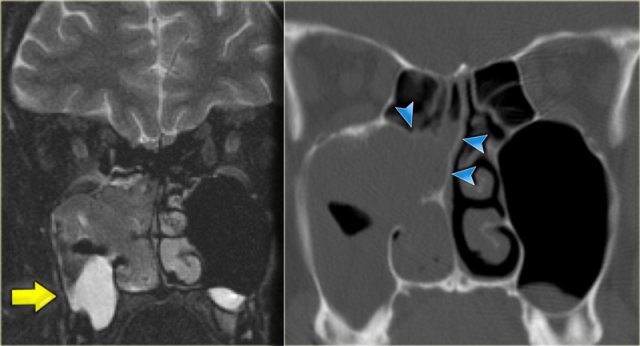

On the left another patient who presented with nasal stuffiness.

Study the images on the left.

Decide for yourself whether you are looking at a solid mass, inspissated secretions, a combination of both or something entirely different.

The pre-contrast T1WI shows a hyperintense area within the maxillary sinus, corresponding to a proteinaceous substance.

Medial to it is an area with hypointense signal similar to the signal in the orbital globes (so probably cystic).

The majority of the soft tissue in the right maxillary sinus is relatively hypointense on the pre-contrast T1WI, but solidly enhances, meaning tumor.

Inverted papilloma in typical location Inverted papilloma in typical location

The T2W-image on the left confirms the cystic element (yellow arrow).

The coronal CT nicely demonstrates remodelling of the bone and expansion (arrowheads).

This proved to be an inverting papilloma.

The localisation is rather typical.